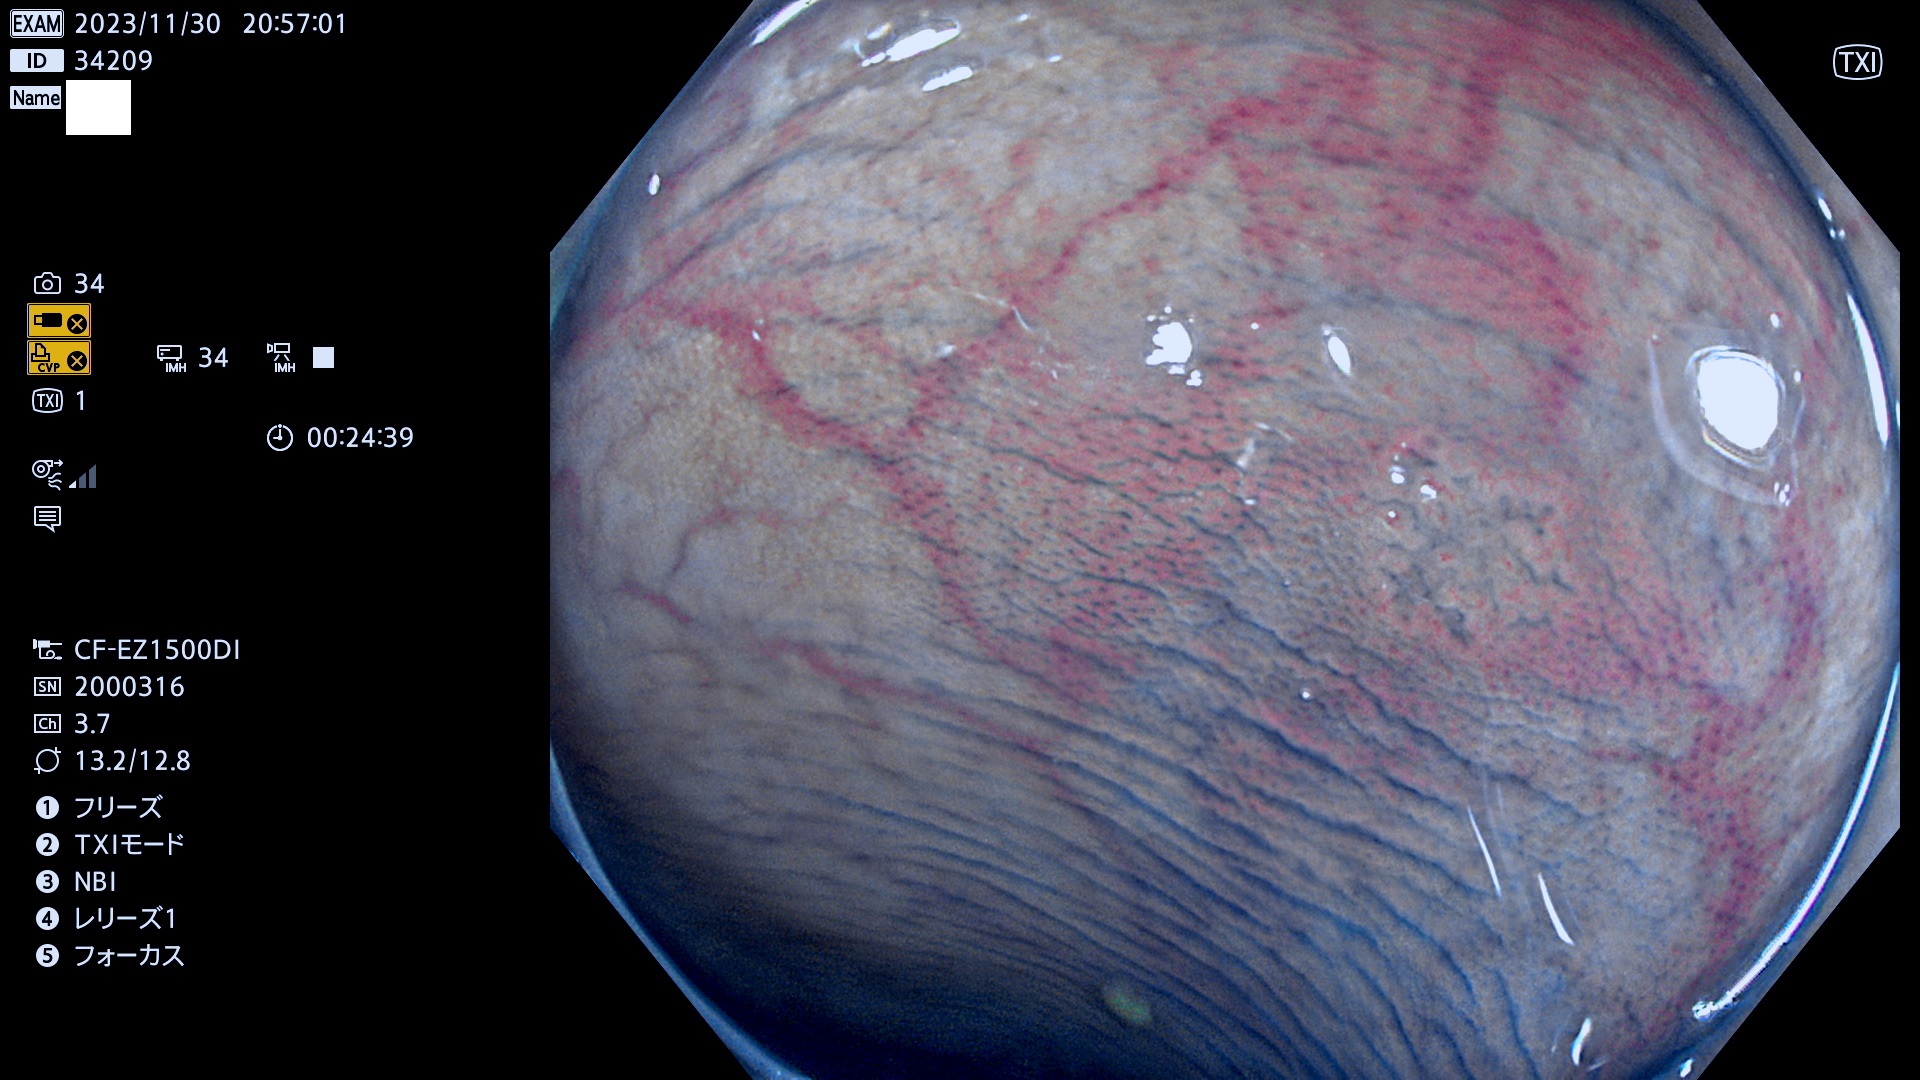

表面型腺腫(Flat Adenoma)の中で、完全に平坦な物をUb、陥凹している物をUcと呼びます。平坦隆起型(Ua)よりも、発見が難しく危険な病変です。このタイプは「内視鏡後・大腸癌の重要犯人」であり、この発見率は「腺腫発見率」よりも、重要な意味があります。

毎週の検査(木・金・土・日)に発見されたUb、Uc型・腺腫を、その週の日曜の夜にUPし1週間、提示します。

抽出の対象期間 2023年11月30日(木)〜12月4(月)の5日間(60件の検査)6件